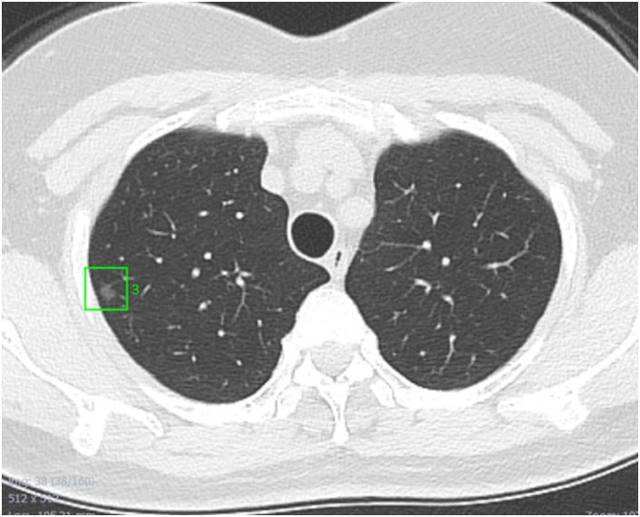

肺部结节是一种病因未明的多系统多器官的肉芽肿性疾病。肺部结节对人体的危害很大,只有摸清肺部结节的成因,才能够在面对结节的时候不至于那么恐慌和担心。发现肺部结节,一定要去找有经验的医生去做检查,并且采取合理的措施进行治疗。

在日常生活中,有些人在体检的时候会遇到肺部结节的病症。肺部结节,如果不加以重视和治疗,容易转换为癌症。只有摸清结节的病因,并找到合理的治疗方案,才能在遇到结节的时候做到有的放矢。那么肺部结节的成因到底是什么呢?以该采取什么样的措施去治疗。

导致肺部结节的原因非常复杂,大致有以下几种情形: 肺部长期受吸烟、空气污染等影响所致的炭末沉着; 肺部良性肿瘤:如错构瘤、硬化性血管瘤、不典型腺瘤样增生(可发展为肺癌)等; 早期肺癌:多为腺癌,尤其是原位腺癌为多;肺部转移瘤;其它:如痰栓、畸形、肺动静脉瘘等。